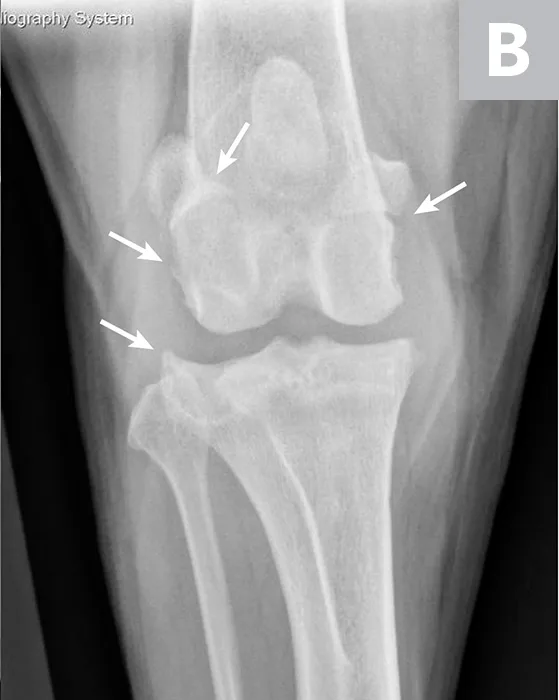

Labeled lateral and craniocaudal radiographs of right stifle showing pathologic features secondary to CCL rupture and medial meniscal tear.

FIGURE 2

Mediolateral (A) and craniocaudal (B) radiograph projections of a 3-year-old spayed mastiff with right CCL rupture and medial meniscal tear. Osteophytes are present on the femoral condyles, patella, fabellae, and tibial plateau (arrows). There is increased soft tissue opacity in the joint space consistent with joint effusion (arrowhead). In addition, there is cranial displacement of the tibia relative to the femur on the lateral projection. These signs combined are consistent with CCL rupture.